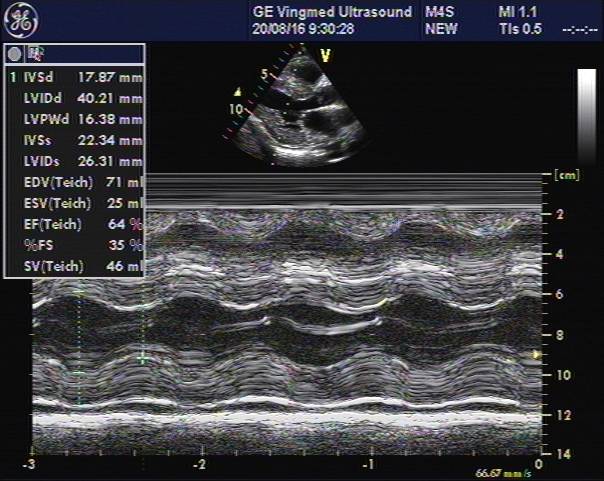

心脏彩超

主动脉根部:30

左室舒张末:40

左室收缩末:26

左房: 34

室间隔: 17

左室后壁: 16

E:79,A:109

EF:64%

E/E’:26